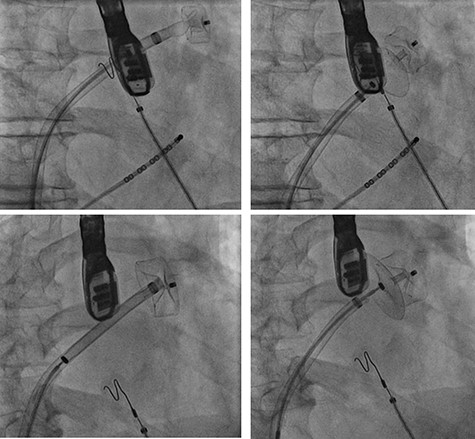

Cardiac catheterization: LAA occluder implantation; interventional LAA occluder implantation via the right femoral vein and septal puncture under radioscopy and transoesophageal echocardiography (TEE) control.

TEE for interventional LAA occluder implantation; TEE controlled, unsuccessful LAA occluder implantation due to difficult LAA morphology.

The patient’s anatomy showed a large funnel-shaped ostium, with narrow neck and shallow depth and chicken-wing morphology with 90° anterior/frontal angulation. TEE measurements showed a landing zone diameter of ~12–13 mm. A 16 mm occluder was selected. The TorqueVue lock 12F was exchanged via a stiff wire and positioned in the left superior pulmonary vein. No satisfactory position was achieved. For the proximal part, shortly after the ostium with a maximum depth of 12 mm the occluder was too small and exchanged for a 20 mm occluder. This could not be securely positioned; the corpus dislocated in the Timed Up and Go test because of limited contact with the LAA surface. A new transseptal puncture was performed in a more posterior and superior position, the CS catheter removed, and the 7F sheath changed to the SL1. The Amplatzer Amulet 16/20/25 mm LAA occluder implantation remained challenging due to the unusual anatomy with an atypical position of the auricular appendage. Finally the procedure was aborted in favour of a LAA clip.